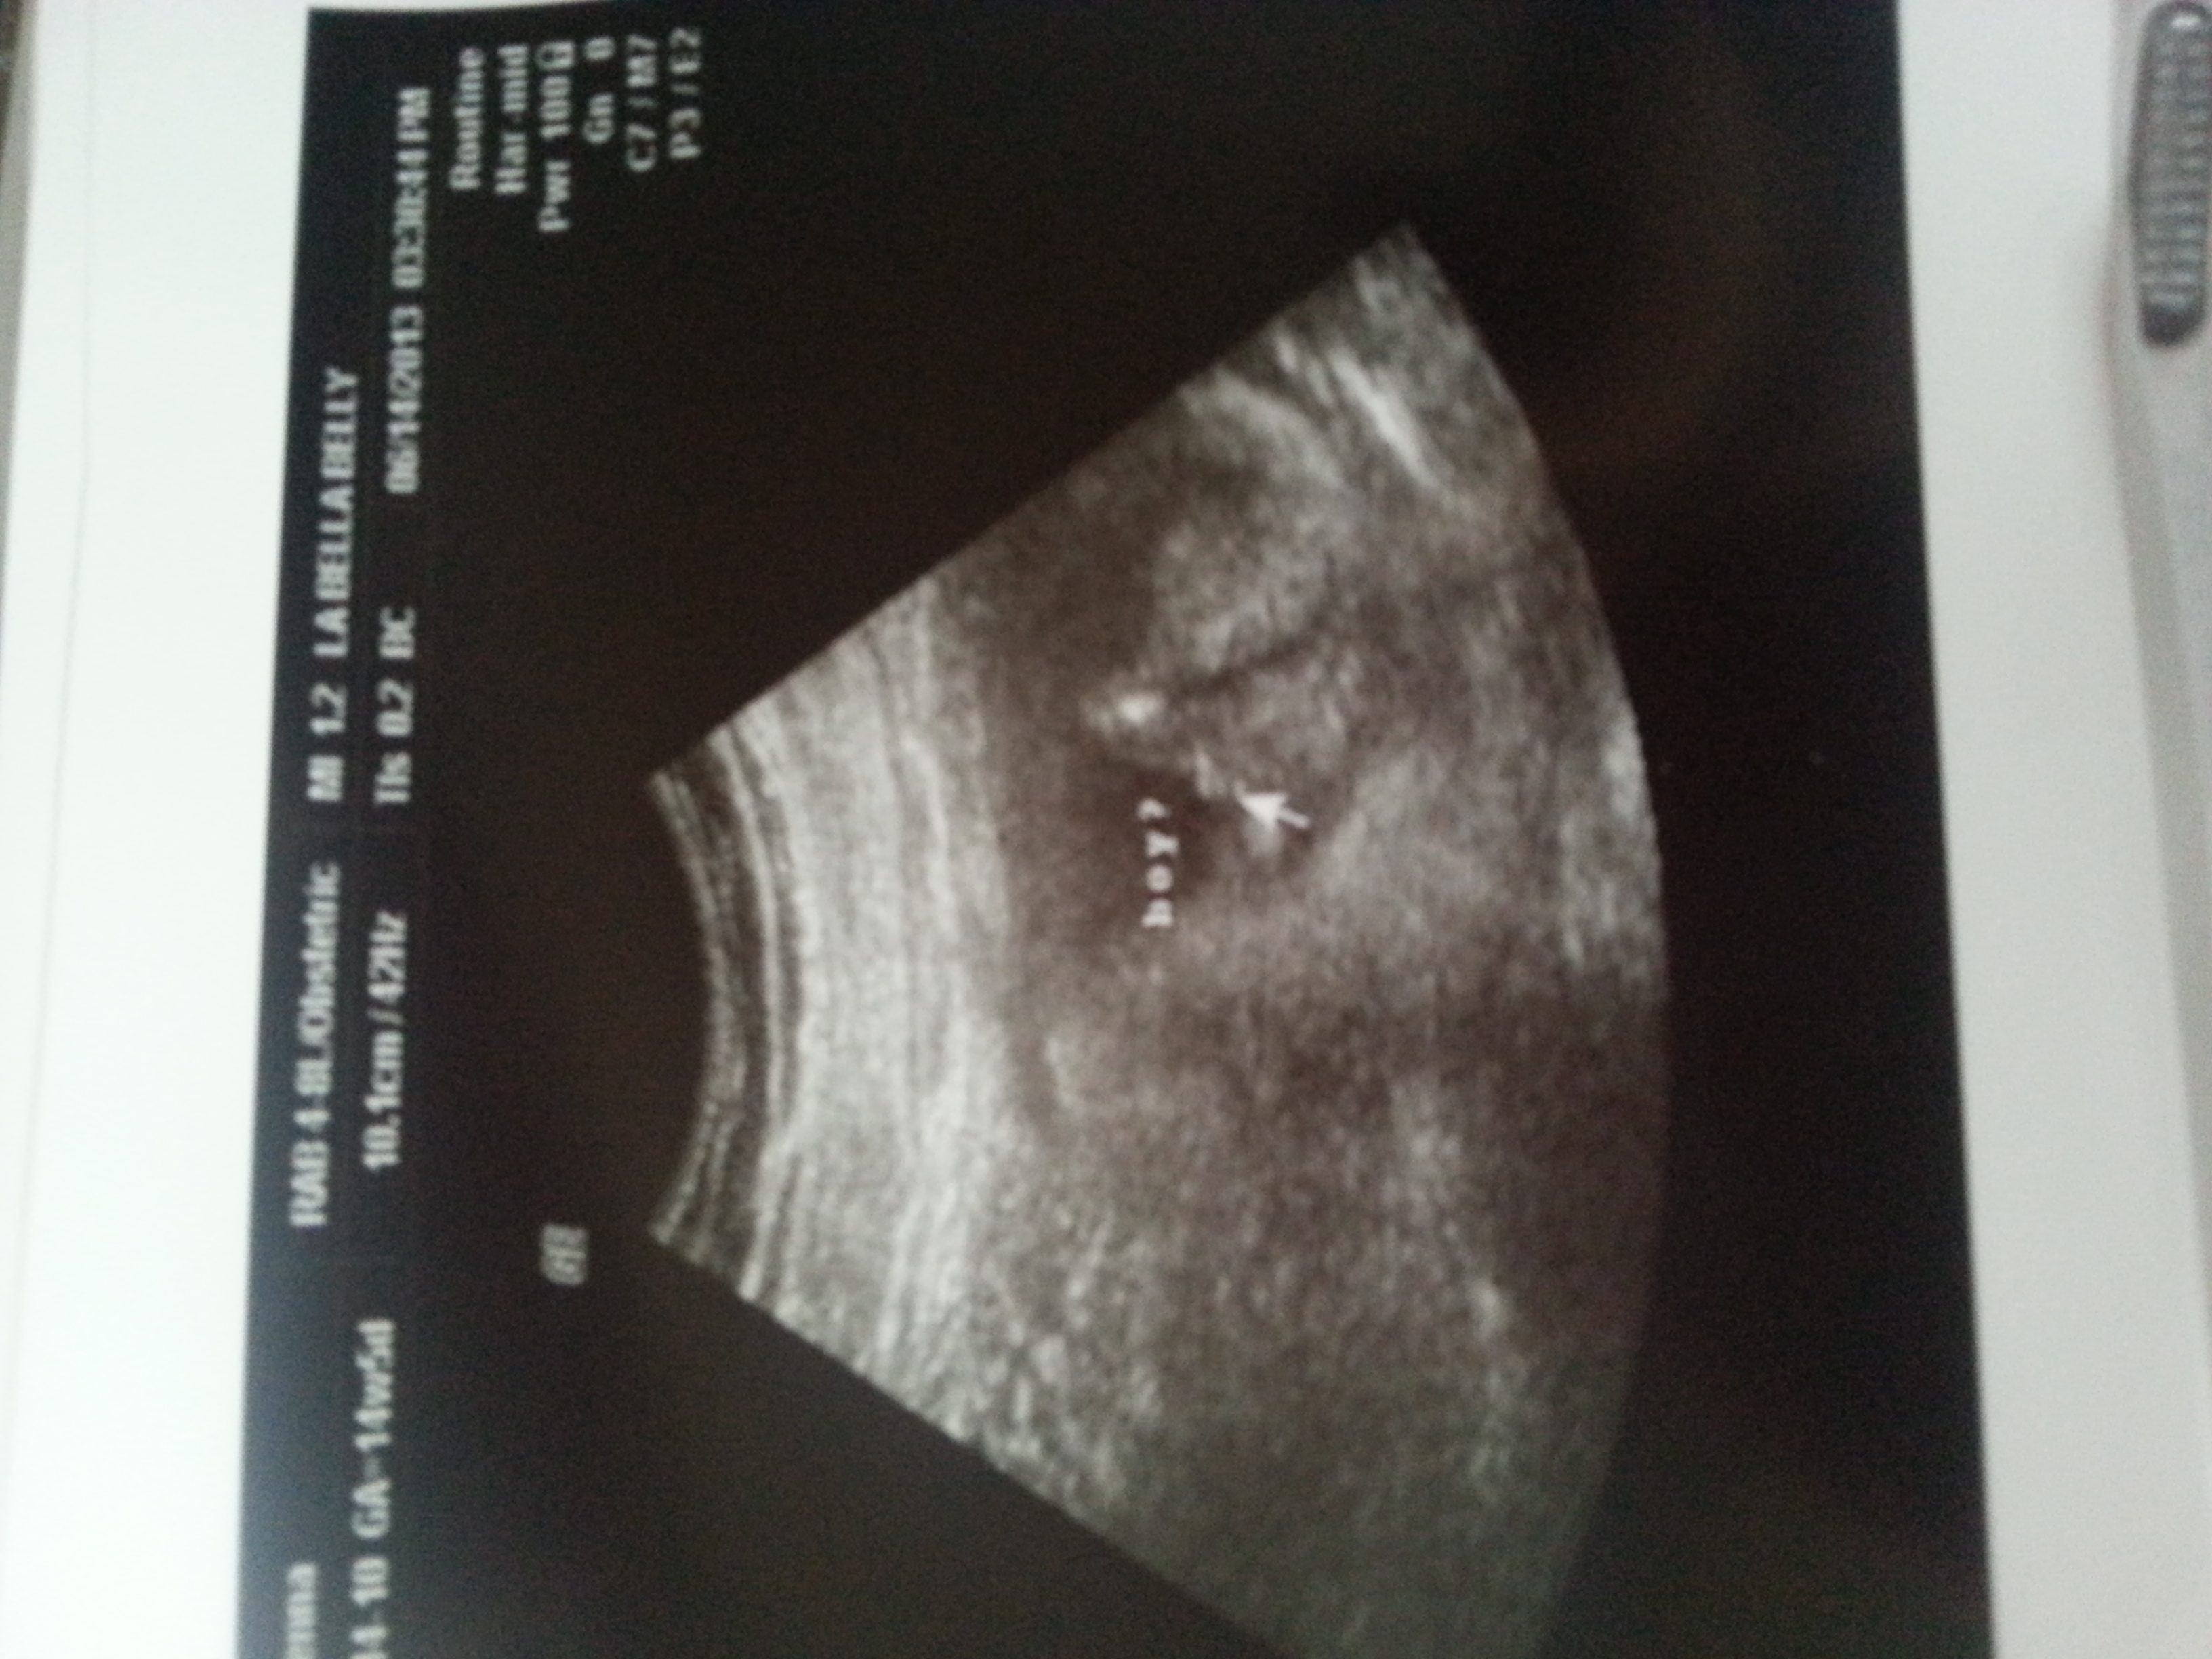

Boy???

Hi all! Just got an elective ultrasound at 14 weeks 3 days and the tech said it is definitely a boy!! I showed the pics to some friends and they told me that the three white dots indicate a girl?? I know 14 weeks is still early. Any ideas if the ultrasound is correct? We will be thrilled with a boy or a girl!

3 dots can look like a girl but your pic looks like my son's at 13 weeks.

A girl would look more like a hamburger. A boy will look more like a pyramid. Like yours does. I think boy too :)